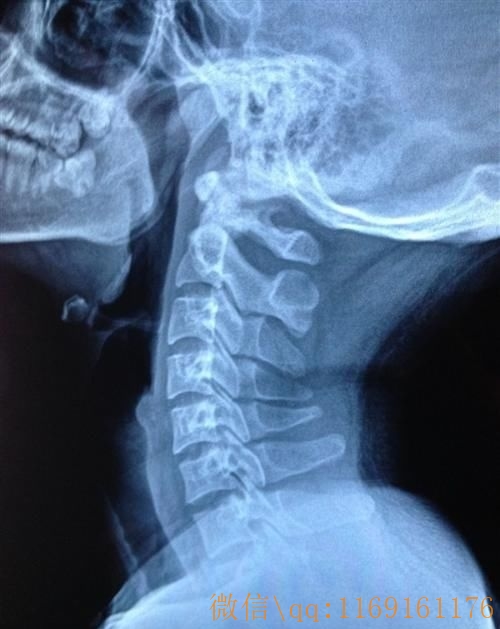

颈椎位于头部、胸部与上肢之间、又是脊柱椎骨中体积最小,但灵活性最大、活动频率最高、负重较大的节段,由于不承受各种负荷、劳损,甚至外伤,所以极易发生退变。大约30岁之后,颈椎间盘就开始逐渐退化,含水量减少,并伴随年龄增长而更为明显,且诱发或促使颈椎其它部位组织退变。生物力学角度来看,第5—6、第6—7颈椎受力最大,因此,颈椎病的发生部位在这些节段较为多见。

颈椎病的发生和加重,还与生物力学有一定关系。颈椎的好发部位之所以最常见于第5—6颈椎,是由于头颈部的负荷(包括自身重量和各种运动的负荷)集中在下颈段,并以5—6颈椎的压应力最大,特别是长期低头伏案的工作者,第5一6颈椎常处于高压力、高扭曲力状态,这样第5—6颈椎最易、最早、最重地引起退变。当然还有其解剖基础,颈椎的椎管矢状径由上而下逐渐减小,最狭窄处为第5—6颈椎,而此处又恰为脊髓颈膨大所在。因此,一旦出现退变,则十分易出现症状。在颈椎骨质增生、韧带钙化等退化造成椎节制动后,生物力学方面的因素会进一步加重颈椎病的病情。颈椎屈曲时,其压力和扭曲力的最大承受椎节逐渐向下转移,而后伸时则逐渐向上转移,从而造成多节段的病变。